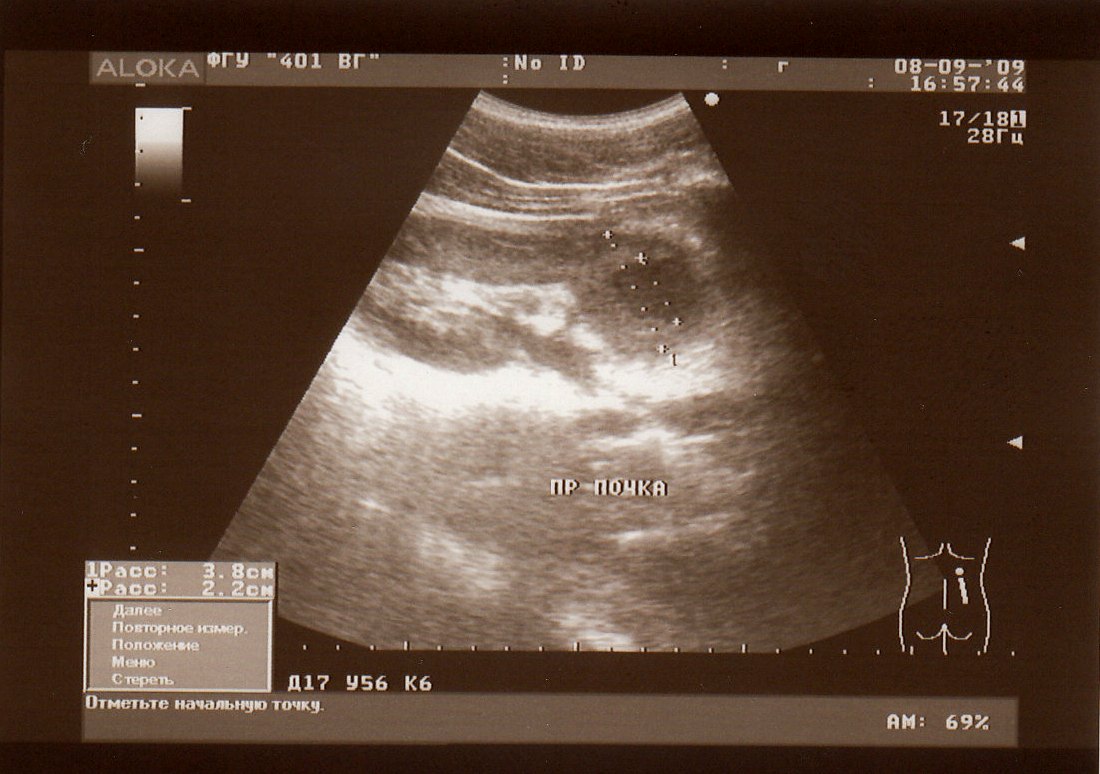

Пациент 19 лет. 8.09.09 поступил в хирургическое отделение госпиталя с жалобами на сильные боли в правой поясничной области. Температура до 38 гр. Кровь воспалительная, в моче белок, сплошь лейкоциты, немного эритроцитов. Прооперирован спустя час после УЗИ. Полное совпадение диагнозов. Прошу мнение коллег, занимающихся ультразвуковой диагностикой.

В области нижнего полюса правой почки лоцируется полостное образование с толстыми стенками, неровным внутренним контуром - абсцесс.

Да, абсцесс почки. Урологи любят их называть карбункулами.